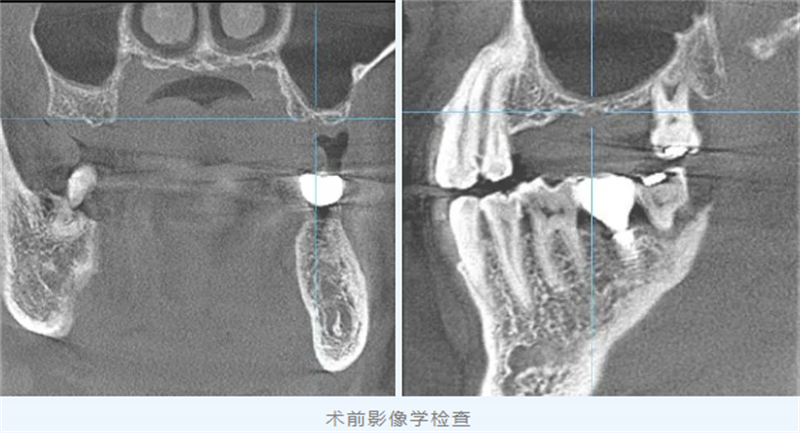

然而,經過詳細影像檢查,醫生發現他左側上頜后牙區牙槽骨嚴重吸收,骨高度僅存約2毫米,這為種植手術帶來了很大挑戰。

面對患者迫切恢復咀嚼功能的愿望,口腔科首席專家黎松齡種植團隊全面評估其骨條件,經過深入討論,最終確定了“上頜骨外提升術”這一治療方案。